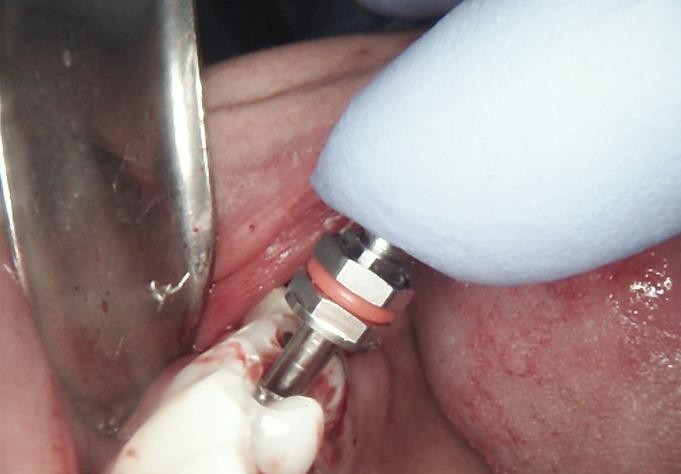

SURGERY

The failed implant was atraumatically removed, followed by thorough debridement of the surgical site.

Bone graft material was placed to restore adequate bone volume and support future implant placement.

A new implant was inserted in a prosthetically driven position, ensuring primary stability.

Surgical site was sutured to allow uneventful healing.